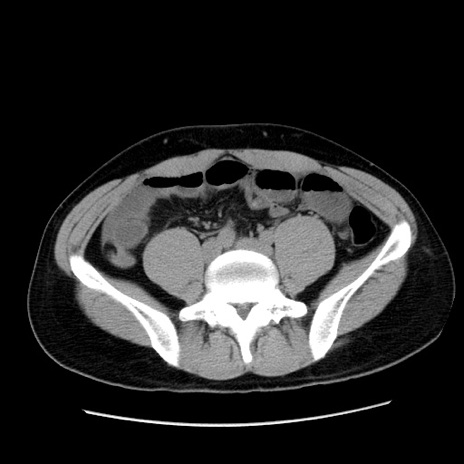

症例36(横断像)

【症例】20歳代 男性

【主訴】心窩部痛

【現病歴】今朝より上腹部痛あり。一旦軽快していたが再度出現したため救急要請。昨日夕に白身の魚を含む刺身を食べた。

【身体所見】BP 136/89mmHg、HR 74/min、BT 37.0℃、腹部:膨満、軟、心窩部に圧痛あり。反跳痛なし、筋性防御なし、腸雑音やや亢進あり。

【データ】WBC 17700、CRP 0.48